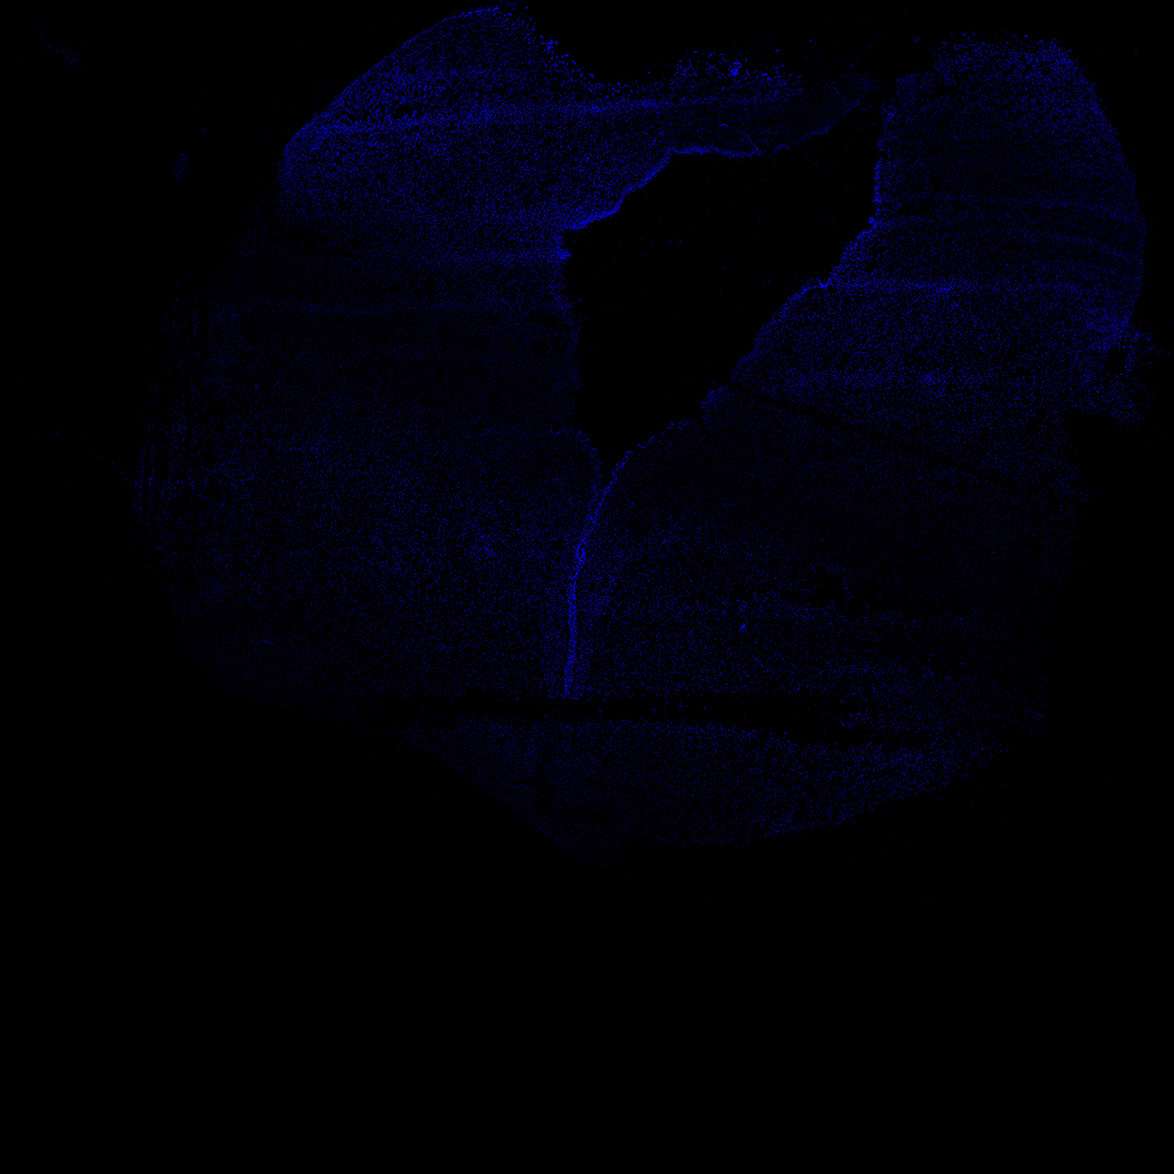

An anatomical analysis of the developing human midbrain from 6 post-conceptional weeks (PCW) to 22 PCW reveals increased tissue complexity, characterized by the emergence of dopaminergic nuclei, as highlighted by immunofluorescence analysis for tyrosine hydroxylase (TH).

DAPI

6PCW human midbrain